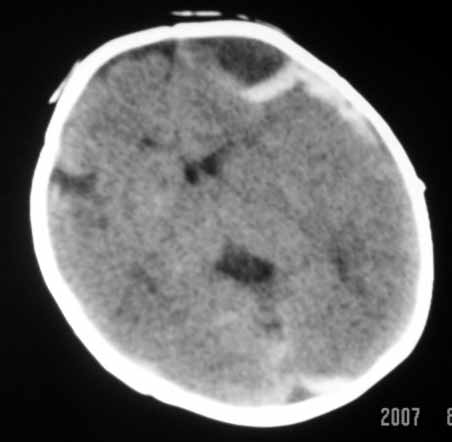

标题: PED0294: 2月婴儿.VitK缺乏症颅内出血.. [打印本页]

标题: PED0294: 2月婴儿.VitK缺乏症颅内出血..

可见 硬膜下及硬膜外血肿,蛛网膜下腔出血

以下是引用jiangjing在2007-8-2 15:07:00的发言:[br]可见 硬膜下及硬膜外血肿,蛛网膜下腔出血

vk缺乏症ct表现有脑实质内出血,珠网膜下腔,硬膜下出血,硬膜外出血,脑实质内出血少见。本病出血要点出血量大,多部位出血,脑室质出血呈团快状。